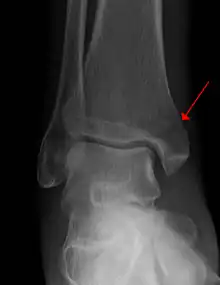

Example of an intraarticular fracture of the medial malliolus extending in the talocrural ankle joint.